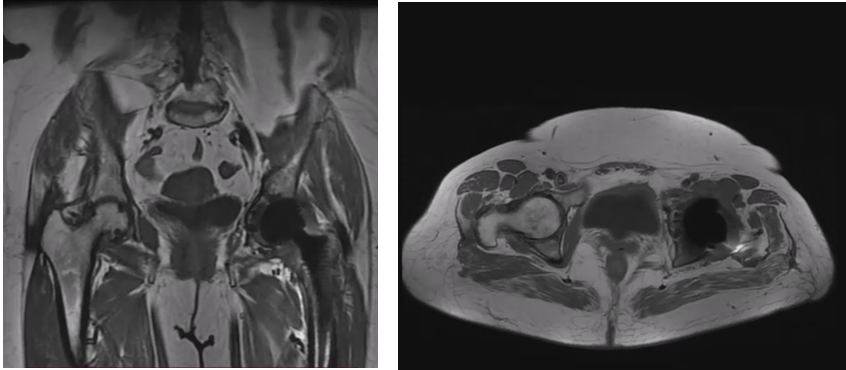

We present a rare case of a 57-year-old female with persistent pain of the hip shortly after THA, who was diagnosed with loosen acetabular cup using dynamic radiographs, while no findings of osteolysis were present either in plain radiographs or computed tomography (CT) and magnetic resonance imaging (MRI) images. The serial imaging revealed movement of the acetabular cup and the decision for revision was made.

Although no instability or gross motion of any of the components was detected intraoperatively, the acetabular cup was fixated with two screws to reinforce the stability of the construct. The post-operative protocol comprised non-weight-bearing for the first 2 weeks, partial weight-bearing for the following weeks and initiation of full weight-bearing at 6 weeks postoperatively. At the 2-month follow-up visit the patient was able to weight bear and walk but complained of pain when rising from the seated position and during the first steps. The symptoms were improving during walking. Clinical examination revealed a leg-length discrepancy of approximately 2 cm, but the radiological evaluation showed no pathological findings. The patient was encouraged to continue rehabilitation, return to moderate daily activities, but to avoid overload. Six months postoperatively, the symptoms significantly worsened with severe pain during loading and a “snapping” feeling on every step. A thorough laboratory investigation was obtained showing no increase in inflammation markers and no other pathological findings. Further imaging with new X-rays, MRI, and CT was also inconclusive (Figs. 3, 4, 5).

Figure 5: Pre-operative evaluation with MRI, no loosening findings.